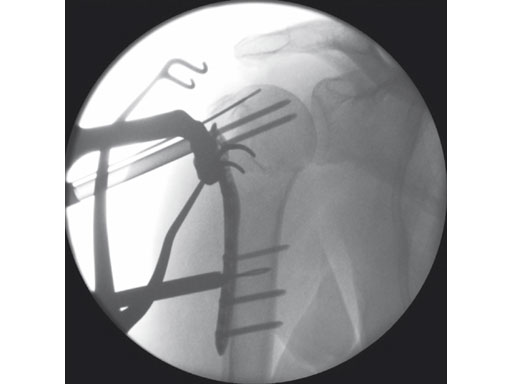

The 3.5 mm LCP percutaneous aiming system for PHILOS offers the possibility to insert the PHILOS plate through the transdeltoid approach and to insert the shaft screws percutaneously enabling a less-invasive application of PHILOS.

The system consists of a sleeve system and an aiming arm. It is used analogously to the existing PHILOS aiming instruments and other aiming systems. The aiming arm is radiolucent to allow control under image intensifier. Locking as well as cortex screws can be used through the device. Compression achieved by cortex screws in the shaft may lead to plate tension. The device has to be locked to the plate at both ends to ensure the plate-device alignment.

A safe zone is defined to protect the axillary nerve (screw holes near the axillary nerve are not accessible through the device). Therefore, the elongated plate hole is not accessible through the aiming arm due to the protected nerve zone. However, by abduction of the arm after fixation, these screw holes become accessible.